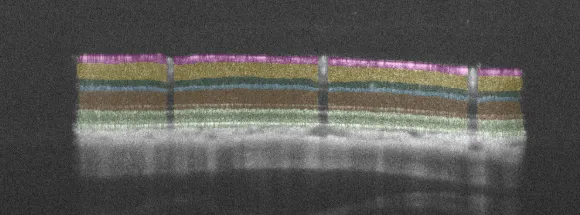

– Quantitative evaluation of inner retinal layer thickness using SD-OCT and AI-driven algorithms

Unbiased quantitative data

From functional to morphological read-outs.

AI for image analysis

AI-driven image analysis for in vivo studies, delivering faster, unbiased results and deeper insights for your preclinical ocular programs.